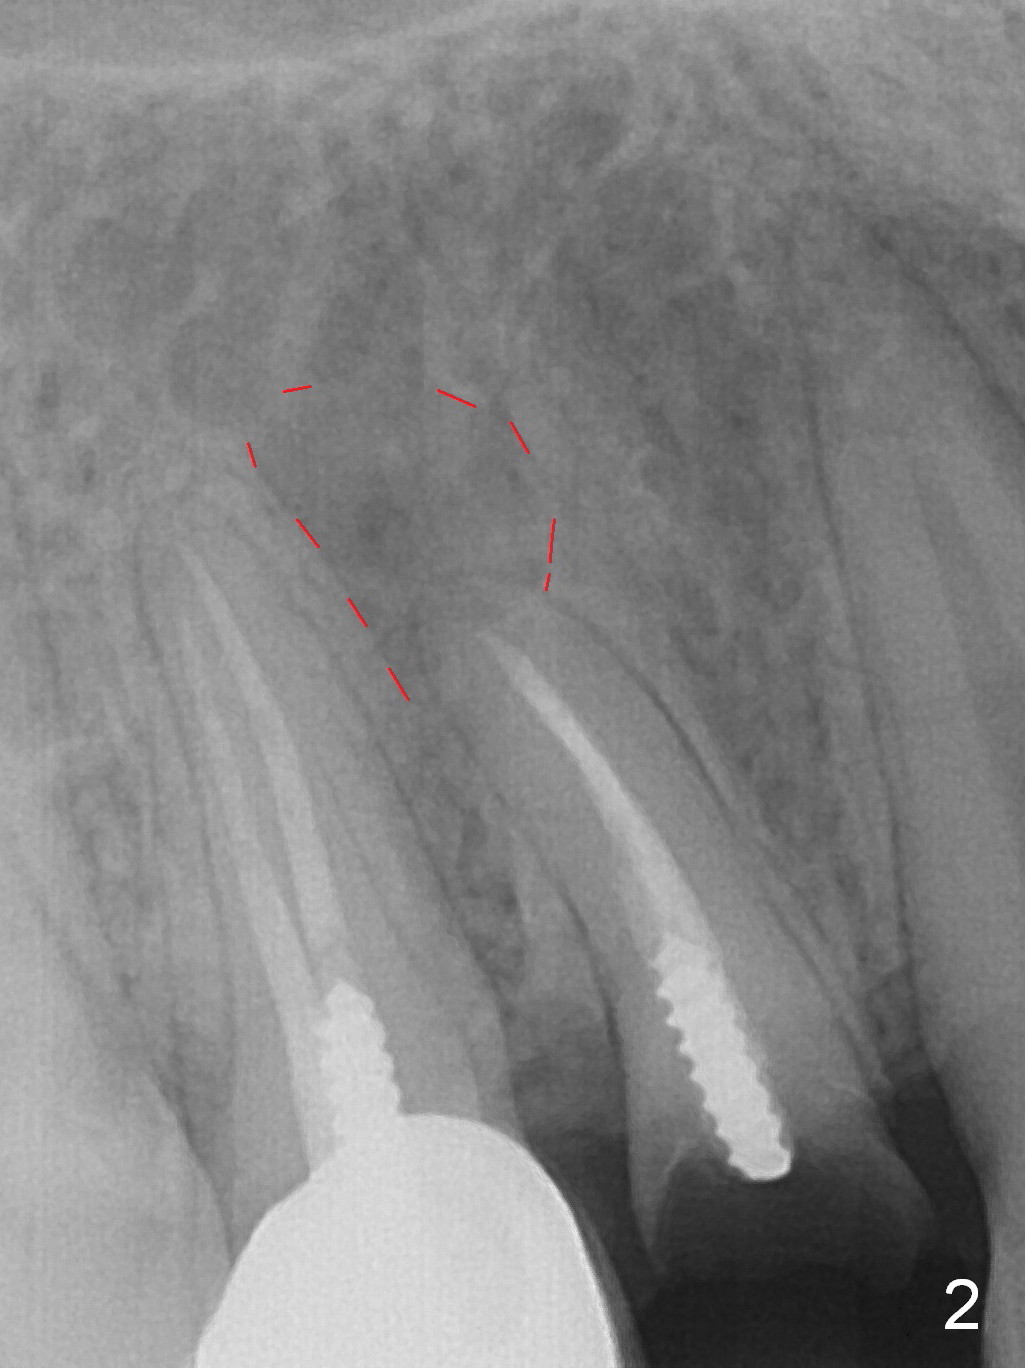

A 34-year-old man (smoker, half a pack a day) has residual root at #5 (Fig.1) with large periapical radiolucency (Fig.2 red dashed line). Since the root curves distally (Fig.3 black area, Clindamycin), osteotomy will be established in the mesial wall (red long arrow). A 3.8x16 or 18 mm implant is to be placed for primary stability (Fig.4). To reduce periimplantitis associated with smoking, place the implant deep. The implant appears to have better surface treatment. Pack sufficient bone graft and membrane. Immediate provisional should have good seal. To place the implant deep, osteotomy will be attempted with a long 1.5 mm pilot drill (PA), followed by 2 mm one with extension and 3.0x18 mm drill.